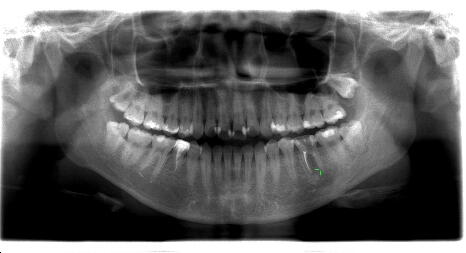

上下顎の第二大臼歯は虫歯になって神経がしんだ場合、根管治療が大変困難で根尖病巣

やのう胞が生じやすい場所です。下の写真は第二大臼歯が保存困難のため抜歯になり、そ のままだと相対する歯が歯の無い所に挺出してくるので、通常は延長ブリッジや部分入れ 歯等になるのですが、親知らずを有効利用し矯正移動させた症例です。 ![]() ![]()

上の写真は埋っていた親知らずを切開して歯冠部をだし、移動させた症例です。

![]() ![]()

下の親知らずを移動させた症例です。下顎の大臼歯の移動は時間がかかります。